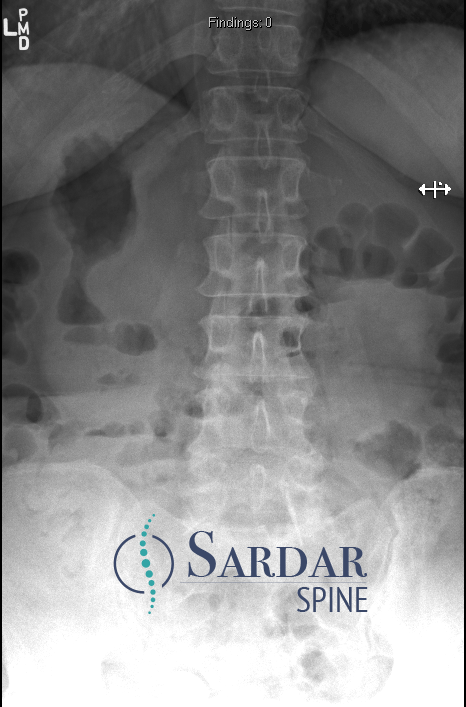

From robotics and AI-driven surgical planning to virtual modeling and custom implants, I’ve embraced a combination of tools that allow me to create tailored surgical plans for my patients—particularly those with scoliosis and spinal deformities.

What sets my approach apart is the seamless integration of these advanced technologies to ensure unparalleled accuracy and better outcomes for each patient.